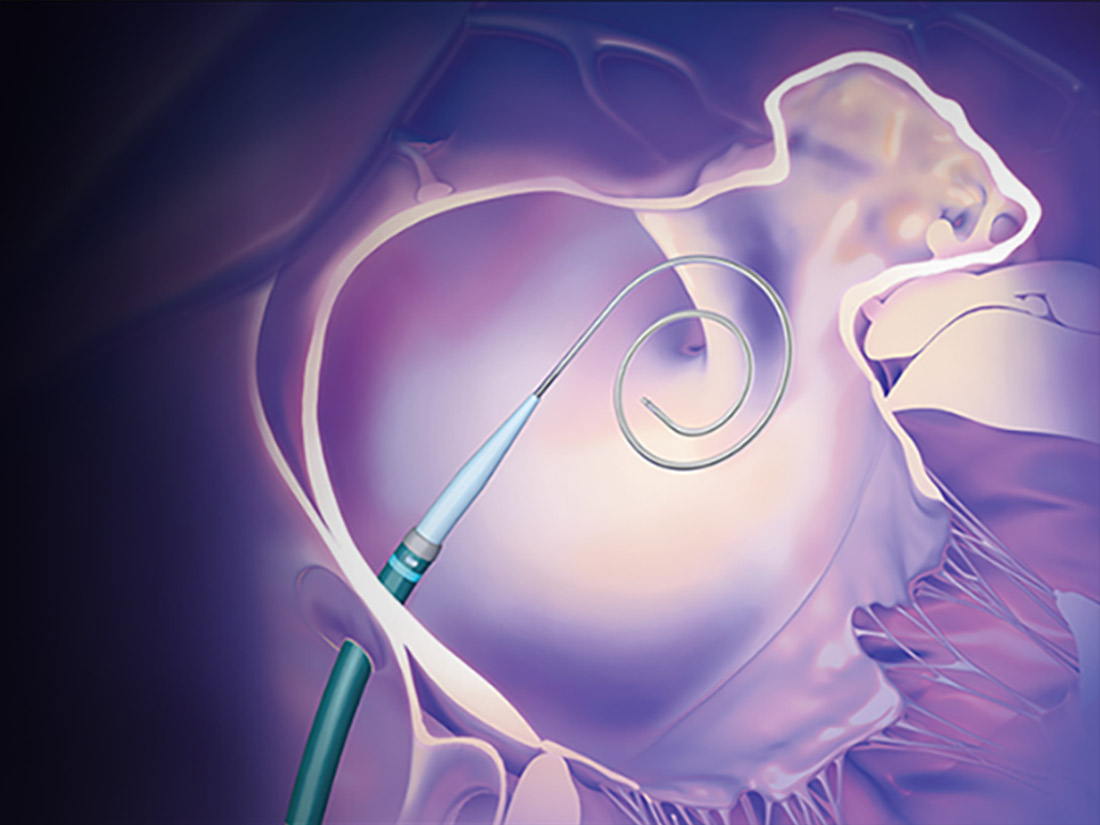

How it works

Discover how the 3-in-1 RF wire and transseptal dilator simplify left atrial appendage closure (LAAC) by connecting the VersaCross Connect Transseptal Dilator and WATCHMAN Access Sheath* for zero exchange left heart access